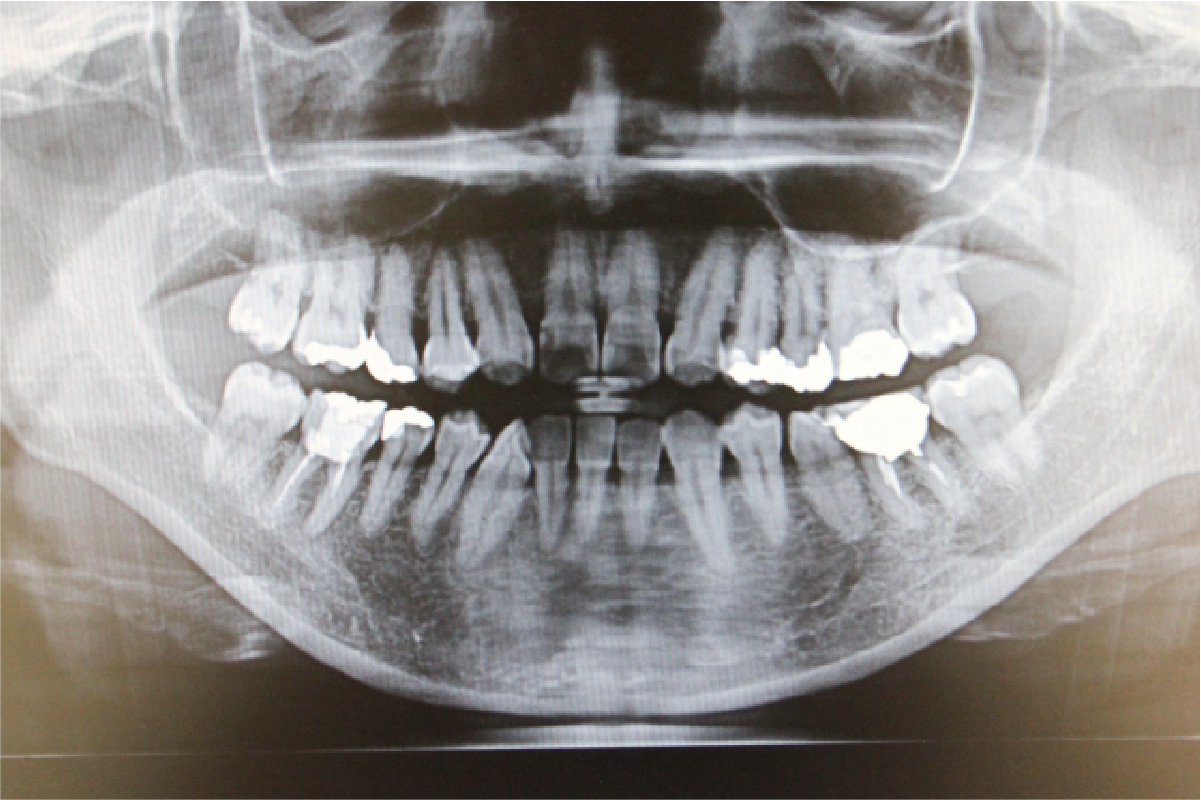

必要に応じて、レントゲン撮影・口腔内写真・歯周ポケット検査などを行い、お口の状態を把握します。目に見えない部分も含めて、現状とリスクを「見える化」し、正確な診断を行います。